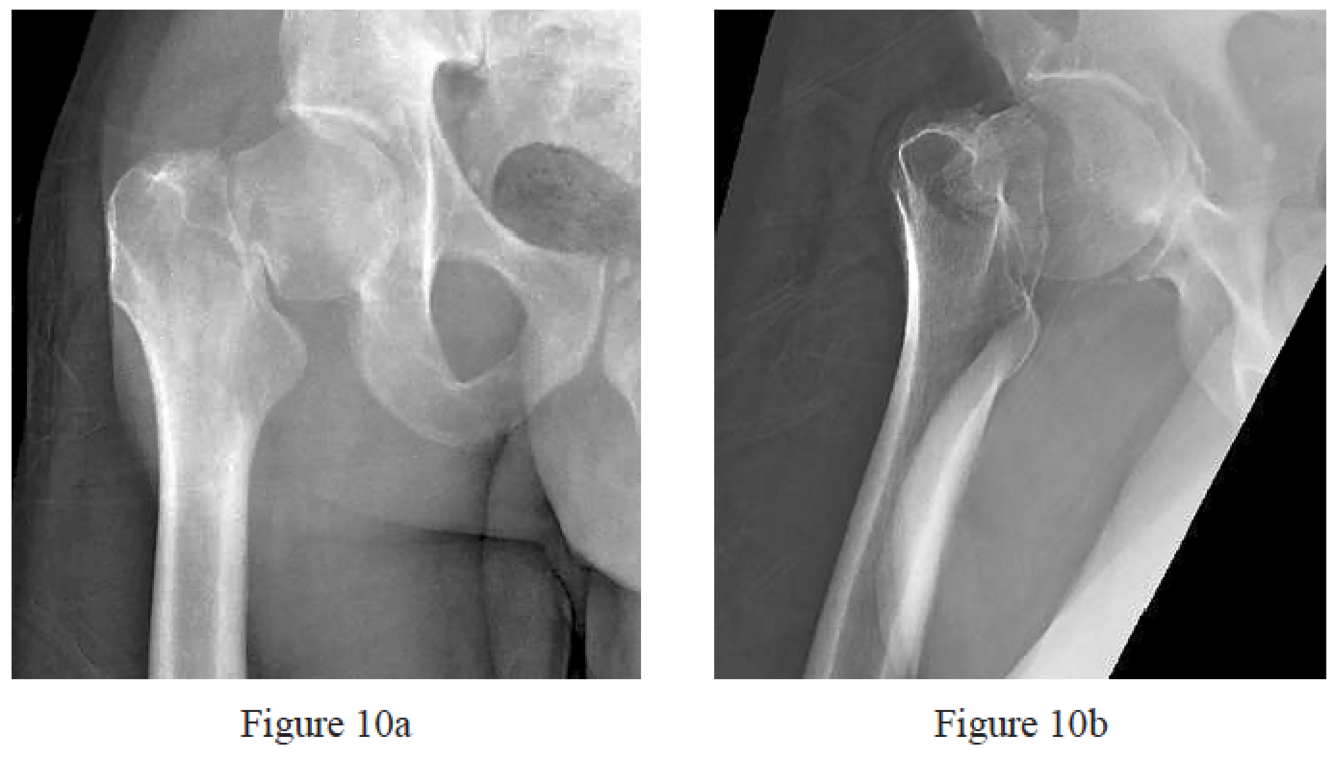

Figures 10a and 10b are the emergency department radiographs of a 32-year-old healthy man who is involved in a motor vehicle collision. He has an isolated injury. What is the best next step?